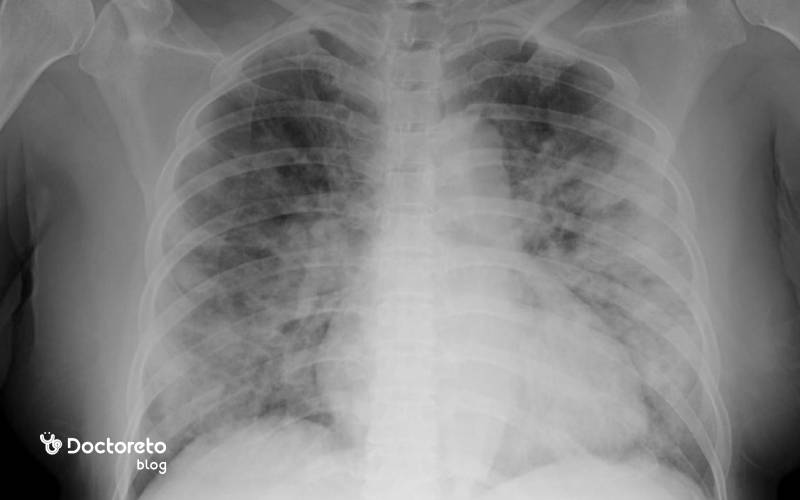

پزشک به الگوی تب، نوع سرفه، درد قفسه سینه و علائم حیاتی توجه میکند و در سمع به دنبال رال، کاهش صدا و علائم درگیری پلور میگردد و سپس رادیوگرافی قفسه سینه را برای تأیید ارتشاح و تعیین وسعت درخواست میکند. در موارد پیچیده یا عدم پاسخ به درمان اولیه، سیتیاسکن قفسه سینه به تعیین پاترن درگیری، وجود آبسه یا آمپیم کمک میکند. آزمایش خون برای سنجش شمارش سلولها و نشانگرهای التهاب و در موارد منتخب کشت خلط برای هدفمند کردن آنتیبیوتیک انجام میشود. سنجش اشباع اکسیژن و در موارد شدید گاز خون شریانی، شدت هیپوکسمی را مشخص میکند. آزمایشهای زیر نیز به تایید تشخیص پنومونی کمکمیکنند:

- عکس اشعه ایکس از قفسه سینه (chest X-ray)

- سی تی اسکن قفسه سینه (chest CT-Scan)

ذاتالریه لوبار الگویی است که در آن یک لوب ریه بهصورت همگن متراکم میشود و تب بالا، لرز، درد پلوریتیک و گاهی هرپس لبیالیس همراه دارد. در رادیوگرافی تراکم لوبی با مرزهای نسبتاً مشخص دیده میشود و در معاینه کاهش صدا و کرکل ریز شنیده میشود. عامل شایع آن استرپتوکوک پنومونیه است، اما عوامل دیگر نیز میتوانند همین الگو را بسازند. درمان سریع پنومونی لوبار با آنتیبیوتیک مناسب، کنترل درد و اکسیژناسیون کافی از عوارضی مانند افیوژن پلور پیشگیری میکند. پیگیری تصویربرداری برای اطمینان از جذب ضایعه بهویژه در افراد سیگاری یا سالمندان توصیه میشود.